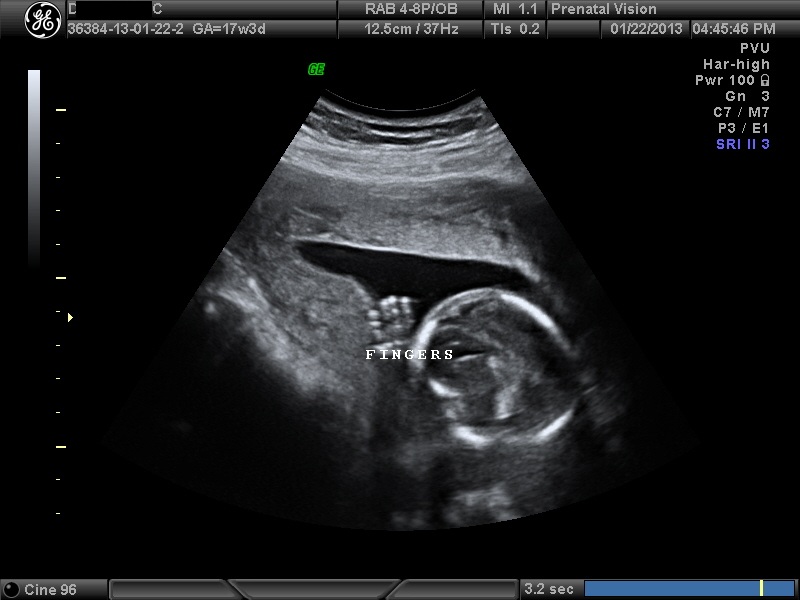

IMAGES_18 January 22, 2013 by Courtney Leave a comment ← Previous Image Next Image → 17w3d Like Loading...